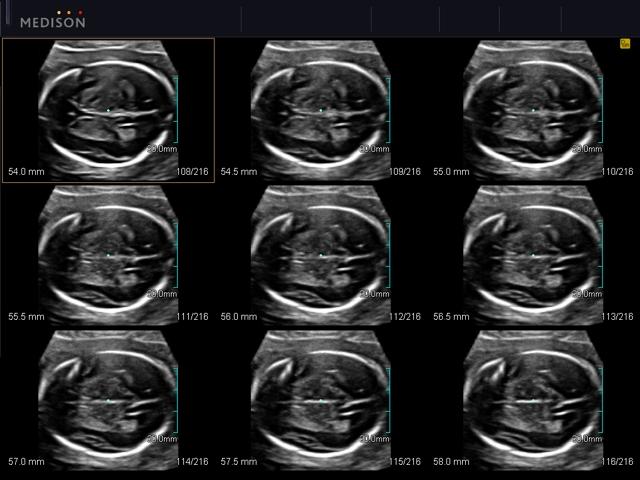

- Ультразвуковая томография (многосрезовый вид): 3D XI;

- - Multi-Slice View (ультразвуковая томография) - возможность одновременного просмотра на экране множественных срезов, полученных при трехмерном сканировании.

Плод, головной мозг, MSV